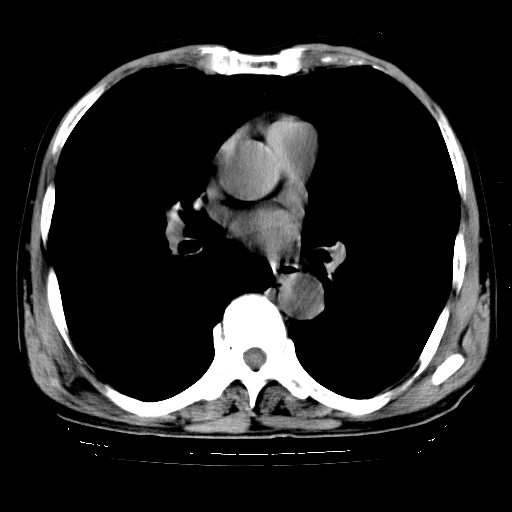

以下是引用hhcckk在2009-1-1 15:38:00的发言:[br]左下肺少许絮状模糊影--考虑感染[br]两肺散在小点状密度增高影--结合病史考虑矽肺?[br]气管壁钙化--可能由于老年退变性引起的